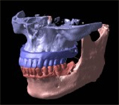

(3)サージカルガイド、サージカルドリルの作製

CTデータ3D立体構築画像によりシミュレーションしたインプラントの埋入位置を高精度に反映した手術用テンプレートを作製します。

手術前に「どこの位置に、どの角度で、どの深さで」などといった細かいシミュレーションが行えます。

また、逆に言うとこのサージカルガイドにより、失敗しようがないほど正確な位置へインプラントの埋入を行なうことができます。

(4)顎の模型を作製

3Dデータから構築した画像を石膏による顎模型を作製します。

骨の状態・歯牙の形状をクリアに再現し、リアルな模型は手術前のイメージ確認やシミュレーションに使用します。